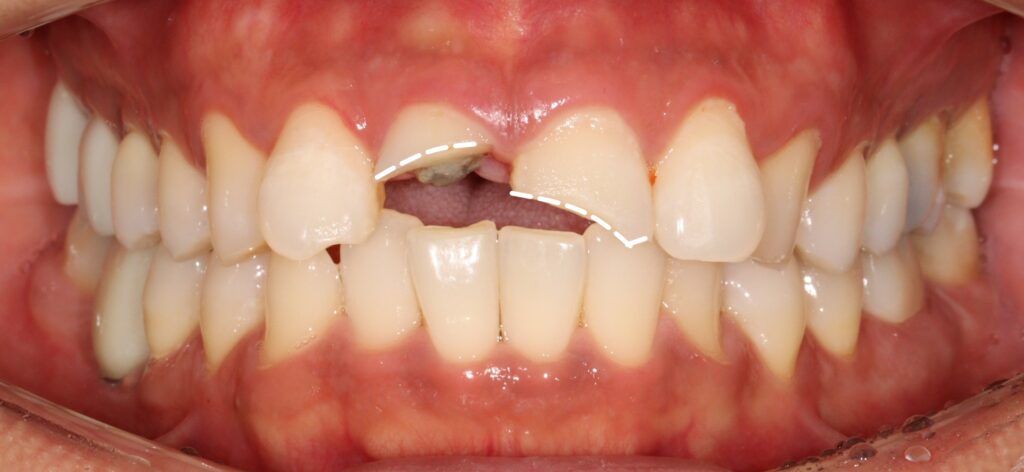

예시 사진을 보면

앞니의 2/3이상이 부러져 사라진 것을

확인할 수 있는데요.

2025.02.12

그로 인해 11번의 경우

자연치 내부 치수가 드러난 것을

볼 수 있으며,

21번은

치수가 드러나지 않았지만

많은 양의 치질이 사라져 있습니다.